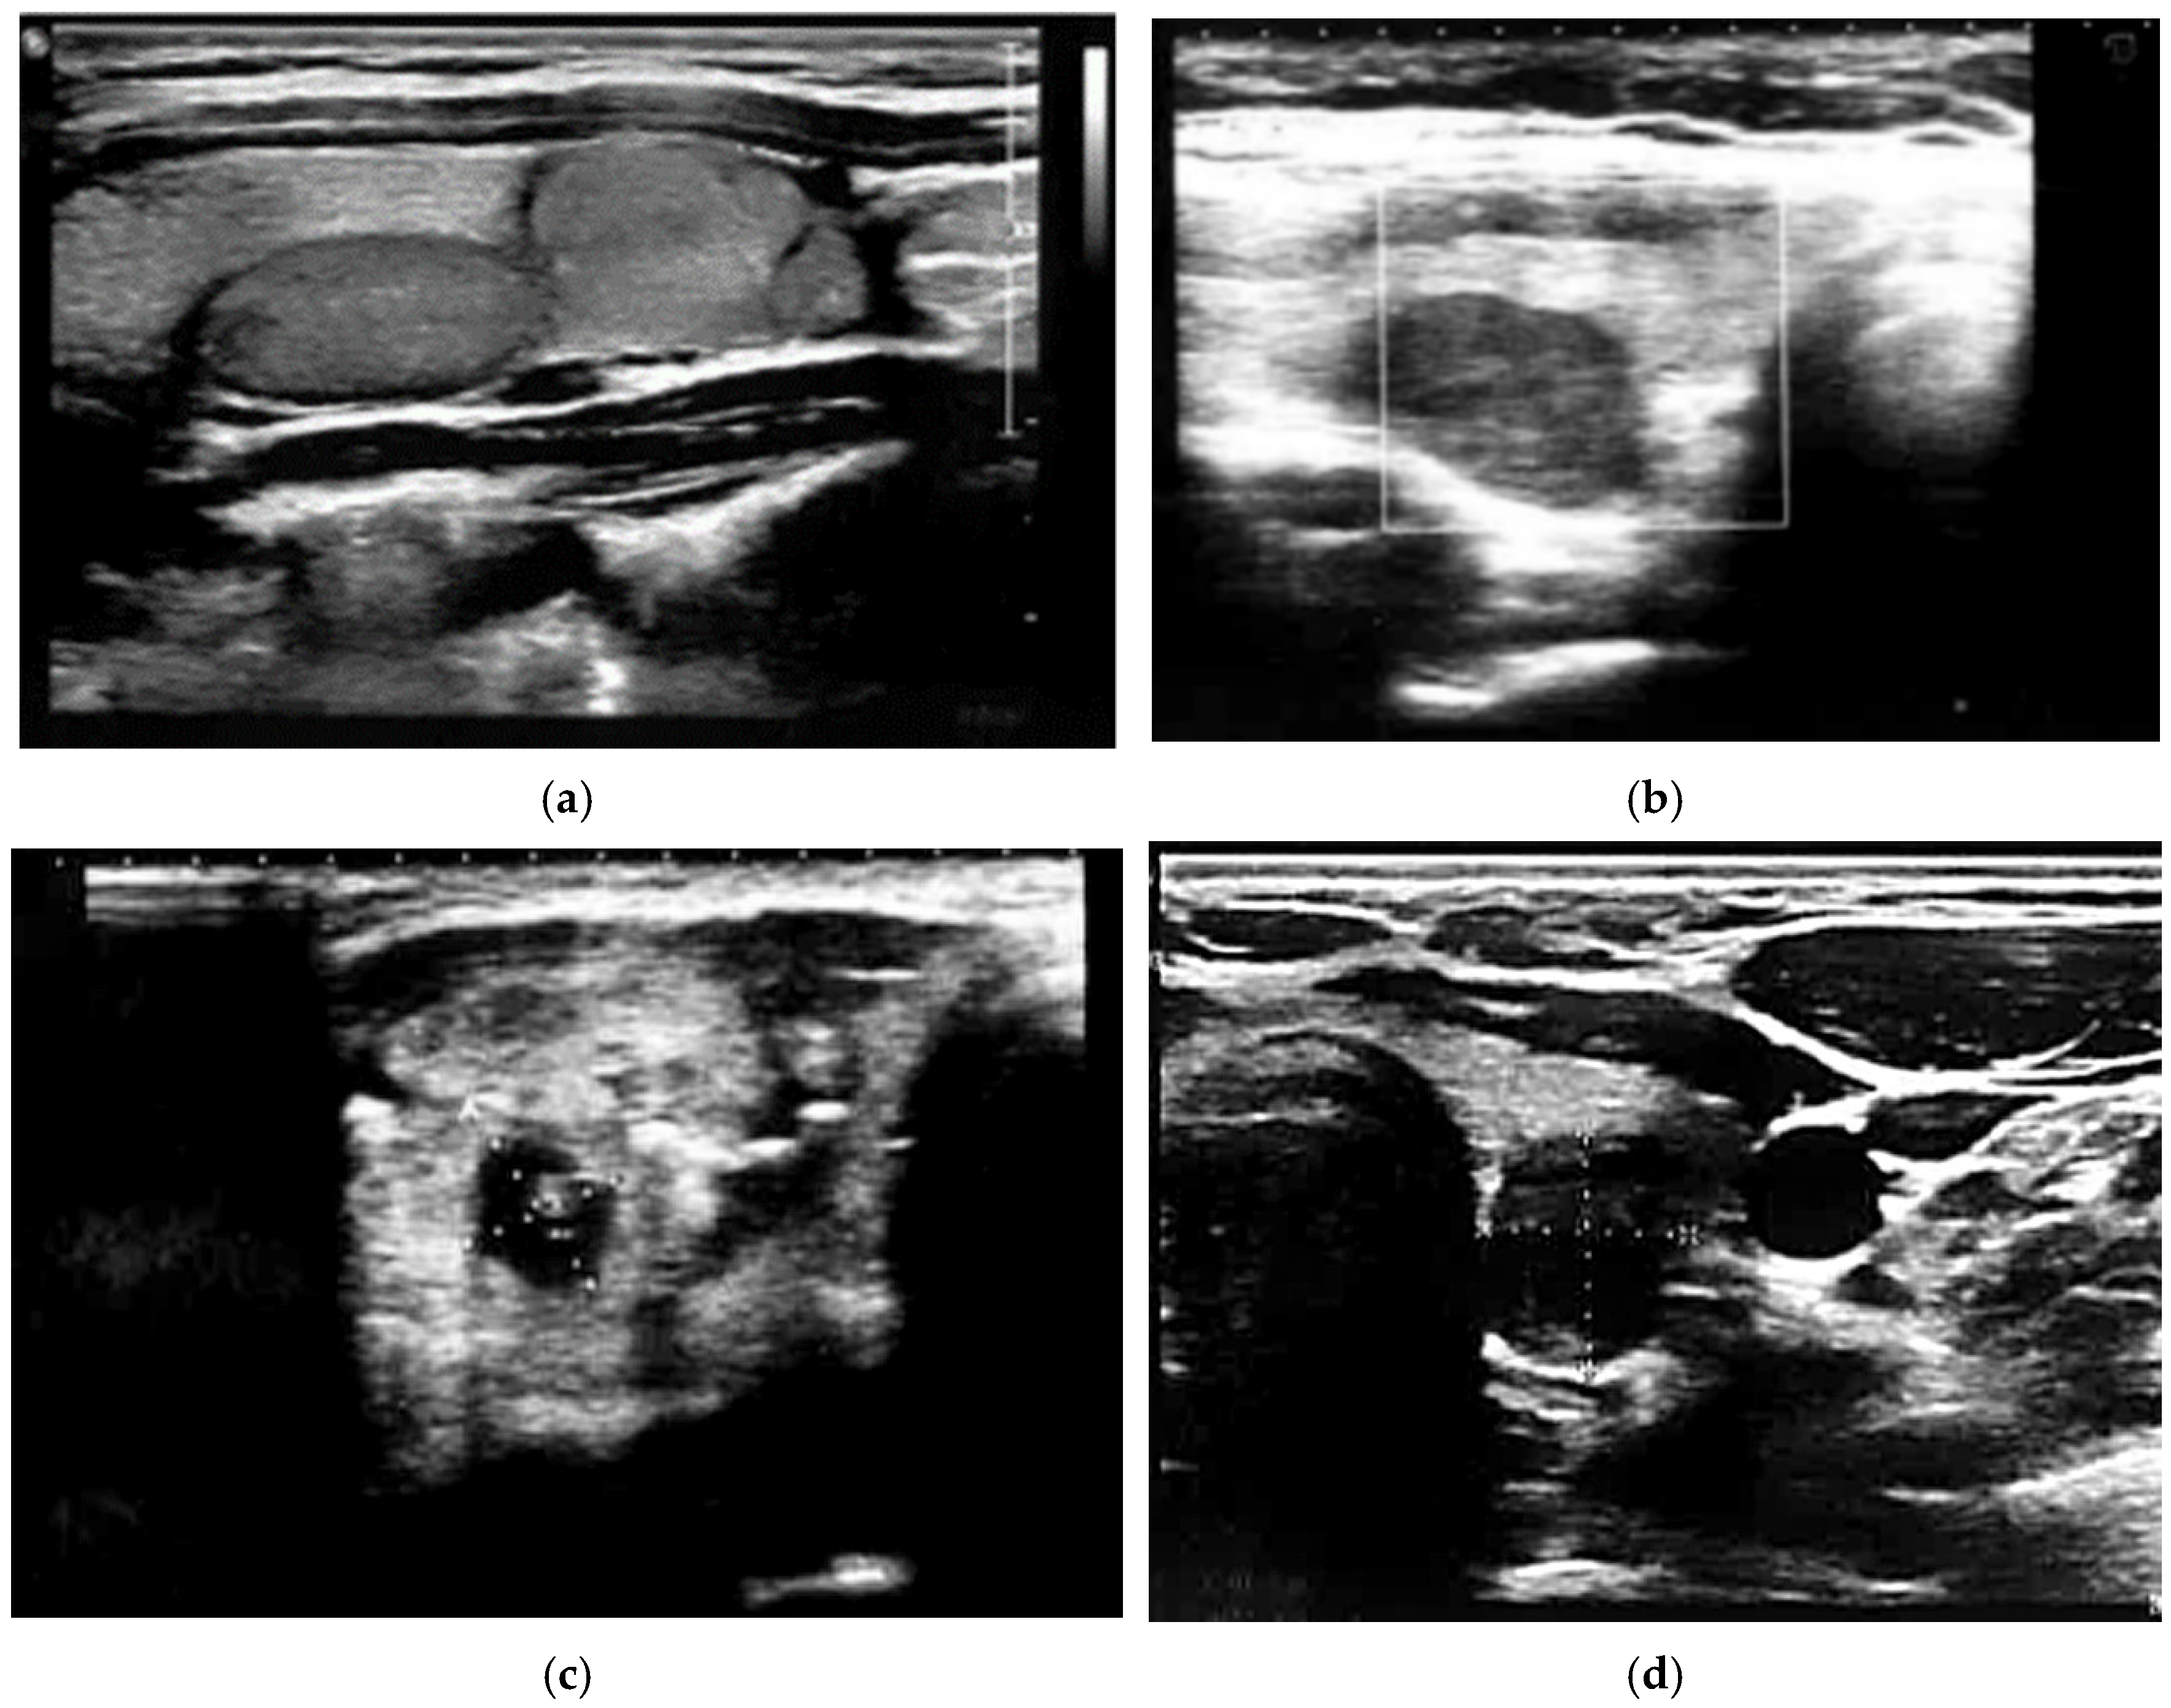

2.3. Thyroid Ultrasonography, Elastography and Fine Needle Aspiration Biopsy

- Januś, D.; Wójcik, M.; Drabik, G.; Wyrobek, Ł.; Starzyk, J.B. Ultrasound variants of autoimmune thyroiditis in children and adolescents and their clinical implication in relation to papillary thyroid carcinoma development. J. Endocrinol. Investig. 2018, 41, 371–380. [Google Scholar] [CrossRef]

- Borysewicz-Sanczyk, H.; Dzieciol, J.; Sawicka, B.; Bossowski, A. Practical Application of Elastography in the Diagnosis of Thyroid Nodules in Children and Adolescents. Horm. Res. Paediatr. 2016, 86, 39–44. [Google Scholar] [CrossRef]

- Cunha, G.B.; Marino, L.C.I.; Yamaya, A.; Kochi, C.; Monte, O.; Longui, C.A.; Cury, A.N.; Fleury, E.D. Elastography for the evaluation of thyroid nodules in pediatric patients. Radiol. Bras. 2019, 52, 141–147. [Google Scholar] [CrossRef]